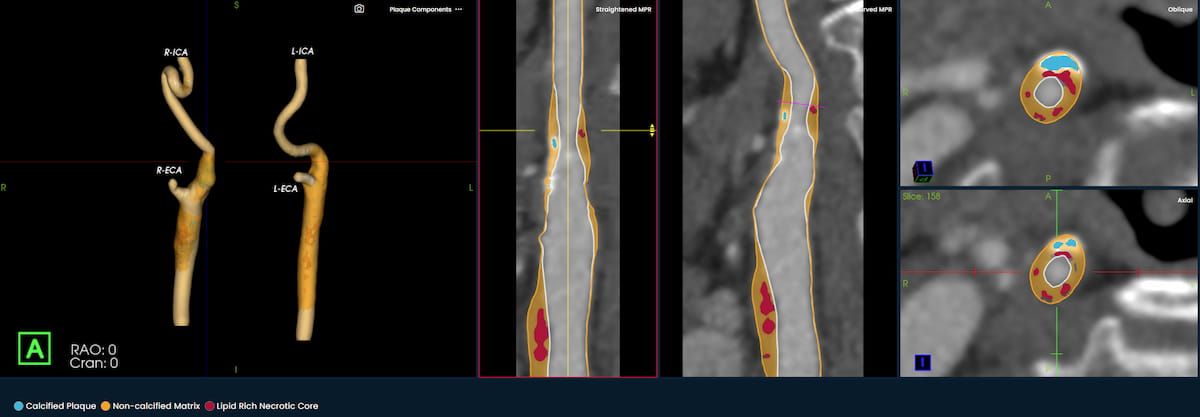

Facilitating timely triage, the qER-CTA software enables AI assessment of the internal carotid artery and M1 segment of the middle cerebral artery for possible large vessel occlusions (LVOs).